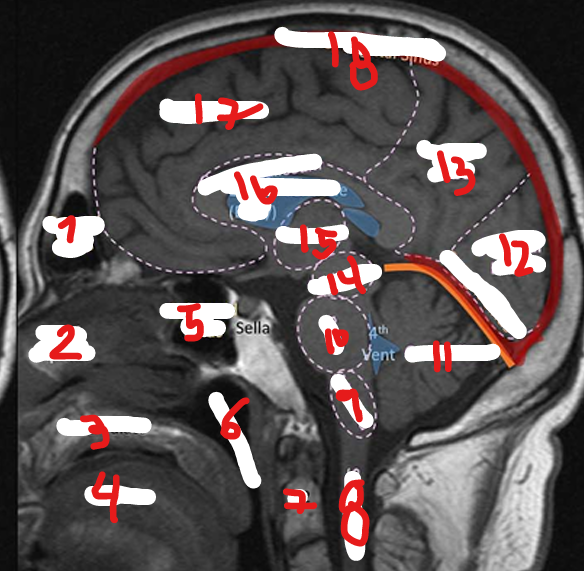

FRONTAL LOBE

1

<p>1</p>

7

New cards

PARIETAL LOBE

2

<p>2</p>

8

TEMPORAL LOBE

3

<p>3</p>

9

INSULA

4

<p>4</p>

10

OCCIPITAL LOBE

5

<p>5</p>

11

CEREBRUM

6

<p>6</p>

12

CEREBELLUM

<p>7</p>

17

<p>17</p>

45

C2

46

SPINAL CHORD

<p>8</p>

47

MEDULLA

<p>9</p>

48

PONS

<p>10</p>

49

<p>11</p>

50

<p>12</p>

51

13

<p>13</p>

52

MIDBRAIN

14

<p>14</p>

53

THALAMUS

15

<p>15</p>

54

CORPUS CALLOSUM

16

<p>16</p>

55

SUPERIOR SAGITAL SINUS

18

<p>18</p>